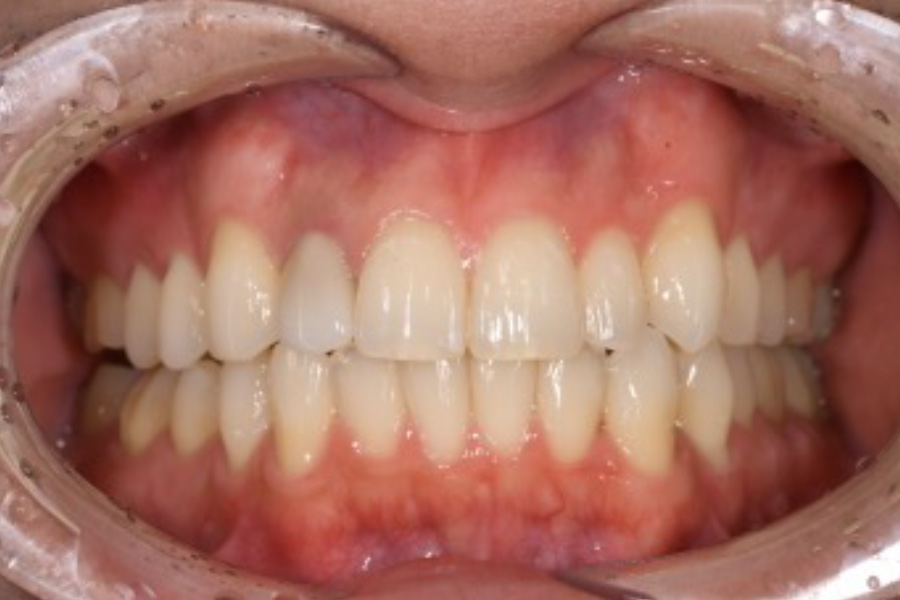

上の前歯が前に出て口ゴボになっている。

歯がガタガタしている。

【マウスピース矯正】

- 上の前歯が前に出て口ゴボになっている。

- 6か月

- マウスピース矯正

839,300円(税込)

- 目立ちにくいマウスピース矯正(非抜歯矯正)

歯と歯の間に隙間をつくることにより、歯列弓を広げながら治療を行いました。

- ・後戻りする可能性があるのでリテーナーを最低でも矯正期間以上はつけること

・稀にほっぺた、唇、舌などに口内炎や傷ができることがあります